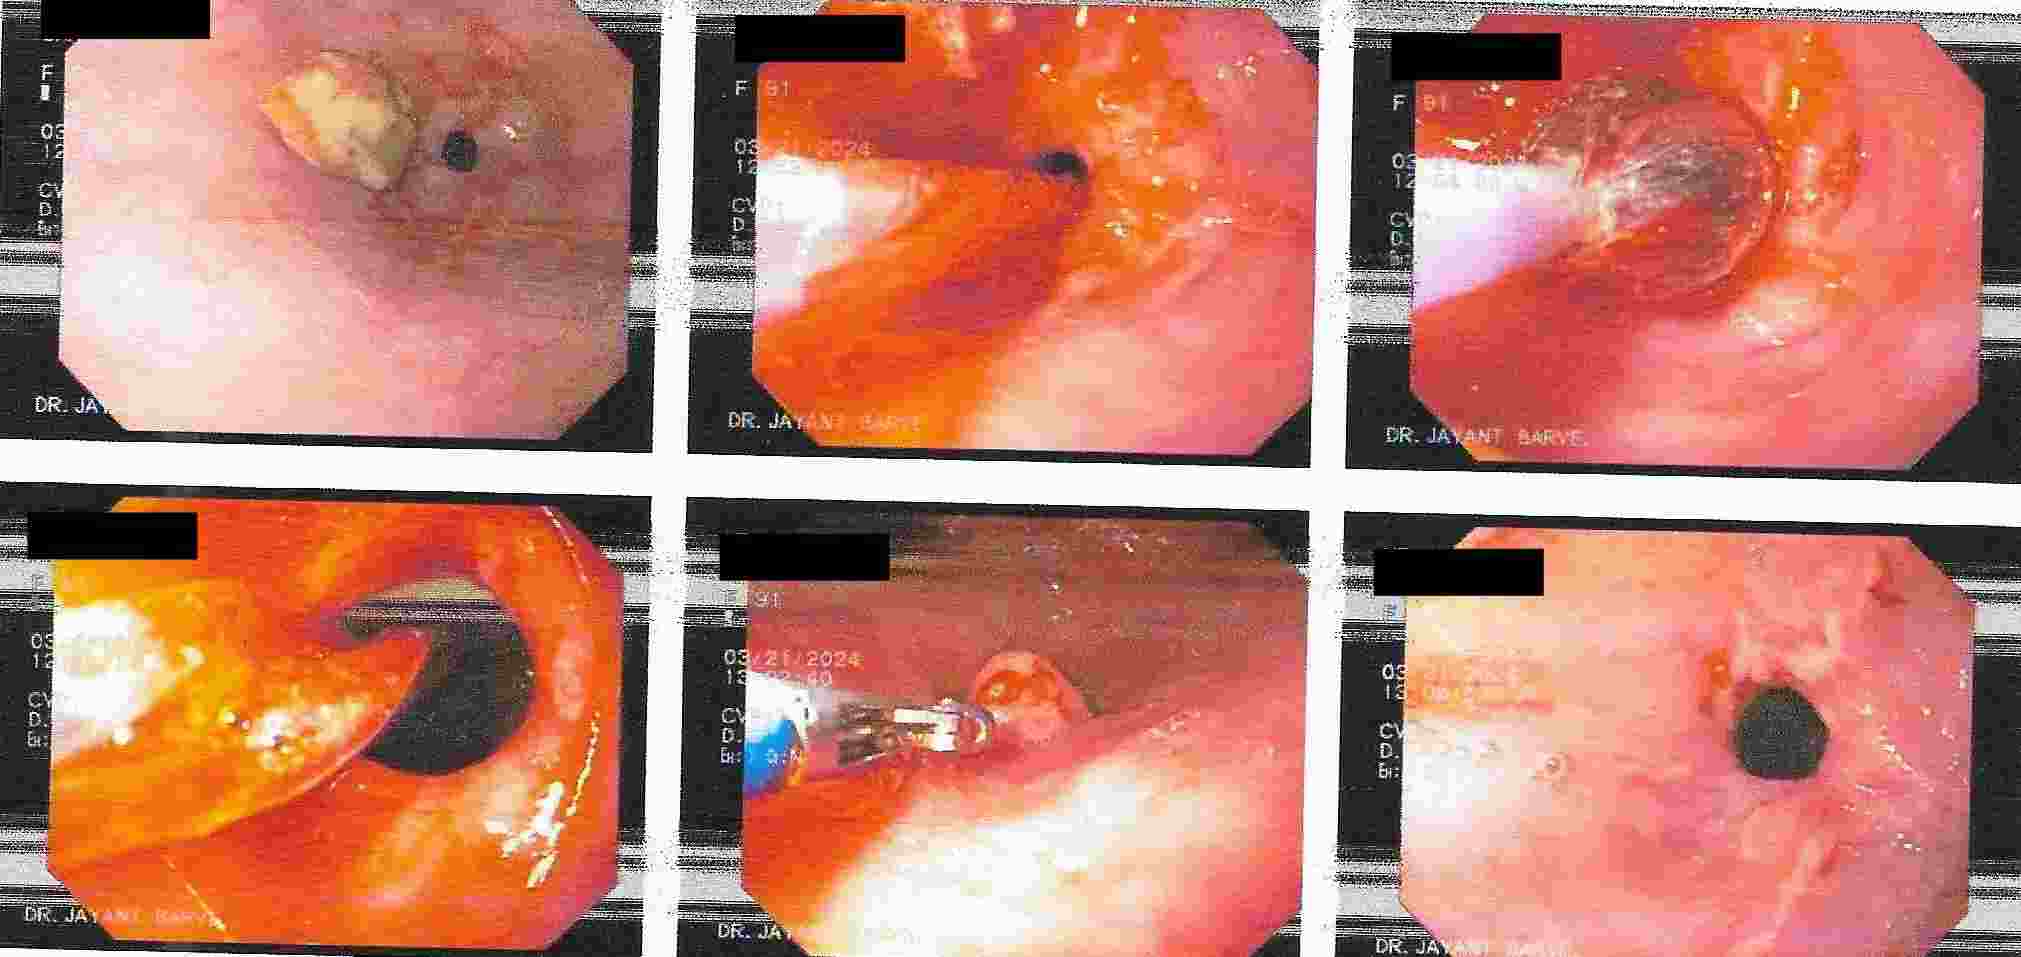

3. Difficulty in swallowing : This is considered as a serious symptom at any age group.

Difficulty in Swallowing

This can be due to severe acidic ulcerations, narrowing of the food passage due to non cancer or

cancerous lesion or pressure on the food pipe from outside.

4. Diagnosis of Hiatus Hernia